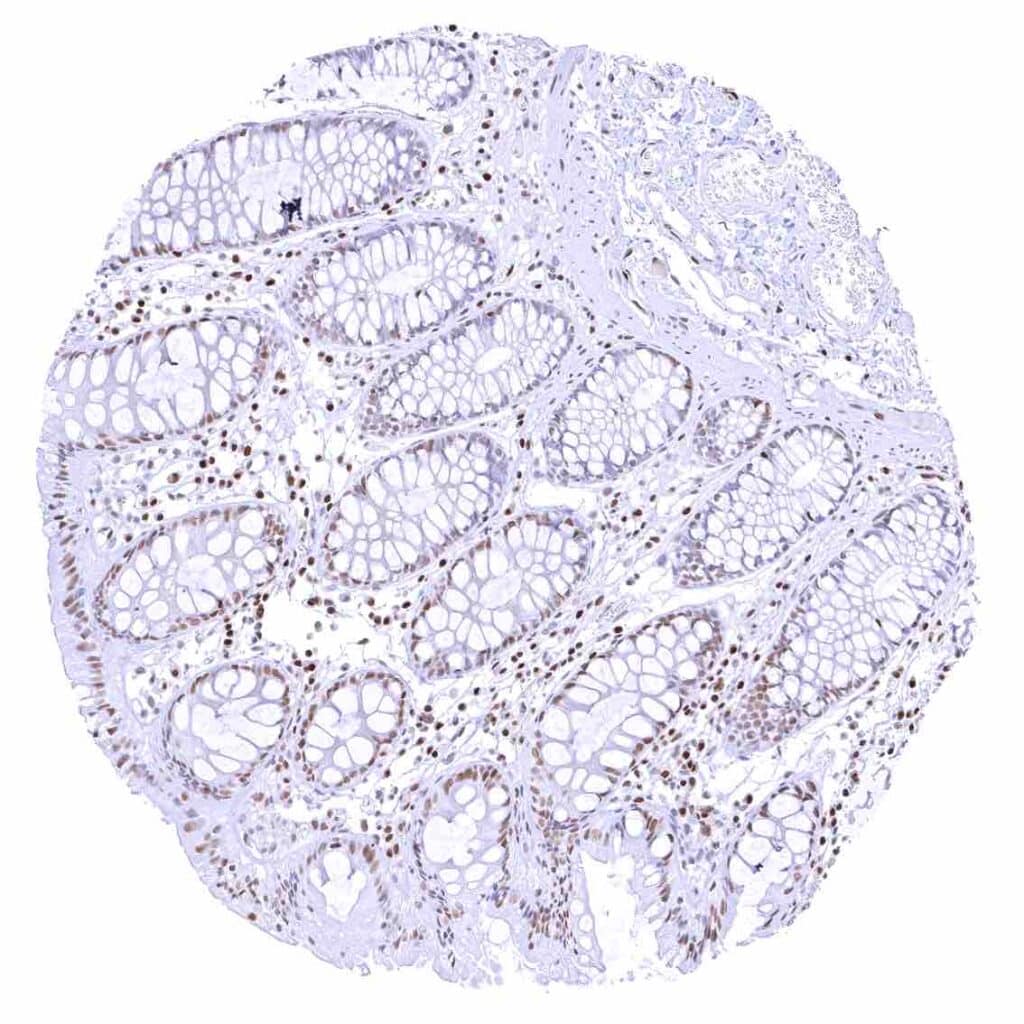

Colon descendens, mucosa